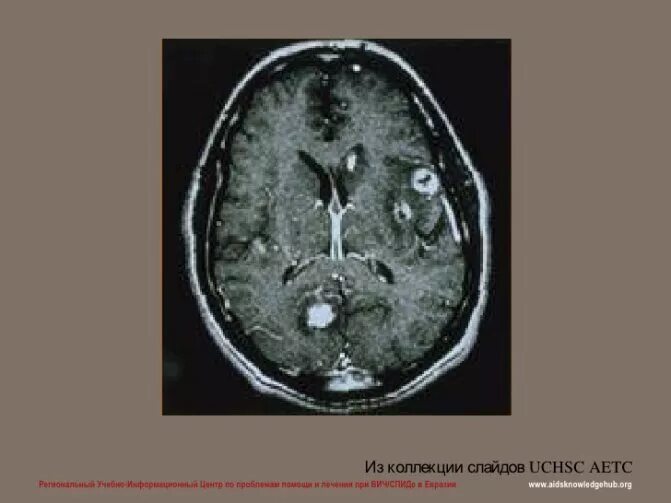

Токсоплазмоз у вич инфицированных